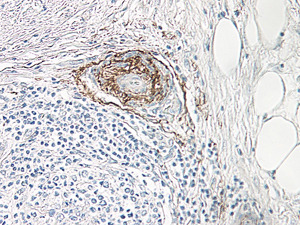

Supportive validation

- Submitted by

- OriGene (provider)

- Main image

- Experimental details

- Formalin-Fixed, Paraffin-Embedded sections of Human pancreas adenocarcinoma stained with beta-NGF Antibody Cat.-No PP1057P at 0.5 ug/ml with an overnight incubation at 4°C. An HRP-labeled polymer detection system was used with a DAB chromogen. Tissue samples were provided by the Cooperative Human Tissue Network, which is funded by the National Cancer Institute.

- Validation comment

- IHC